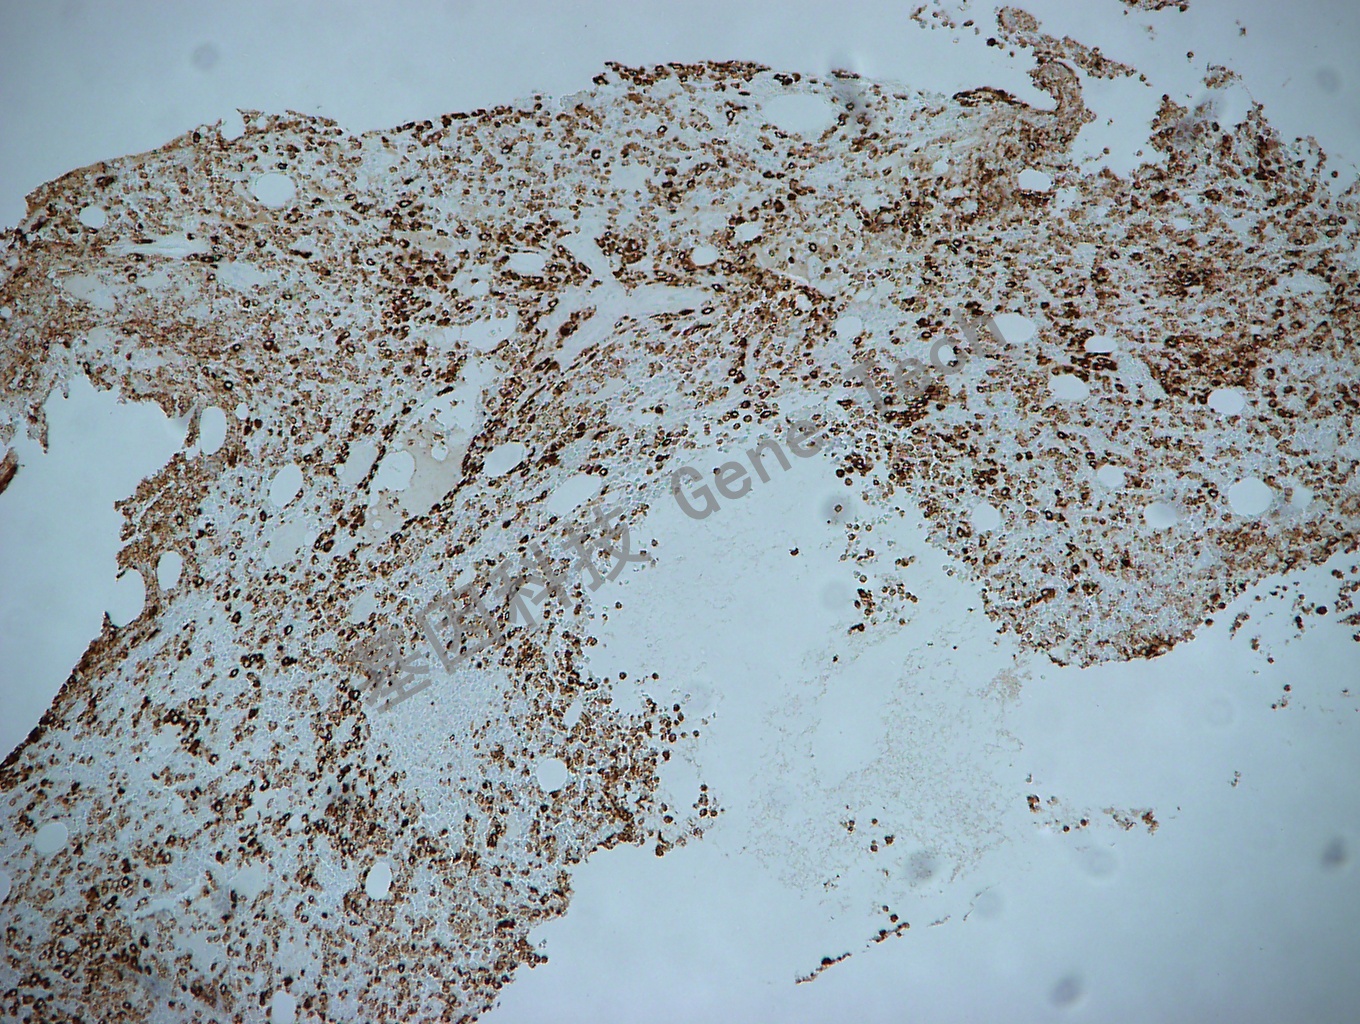

MPO GT2032 胞浆 骨髓10X_副本.jpg骨髓石蜡切片,用 MPO(GT2032)染色,细胞浆阳性,DAB 显色。